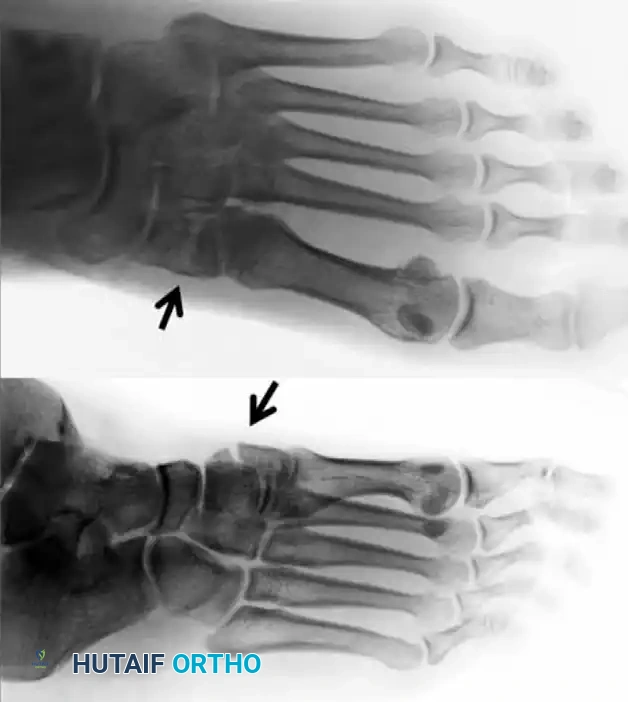

FIGURE 1: Preoperative anteroposterior and oblique radiographs demonstrating a fracture of the medial cuneiform and disruption of the tarsometatarsal articulation (arrows).